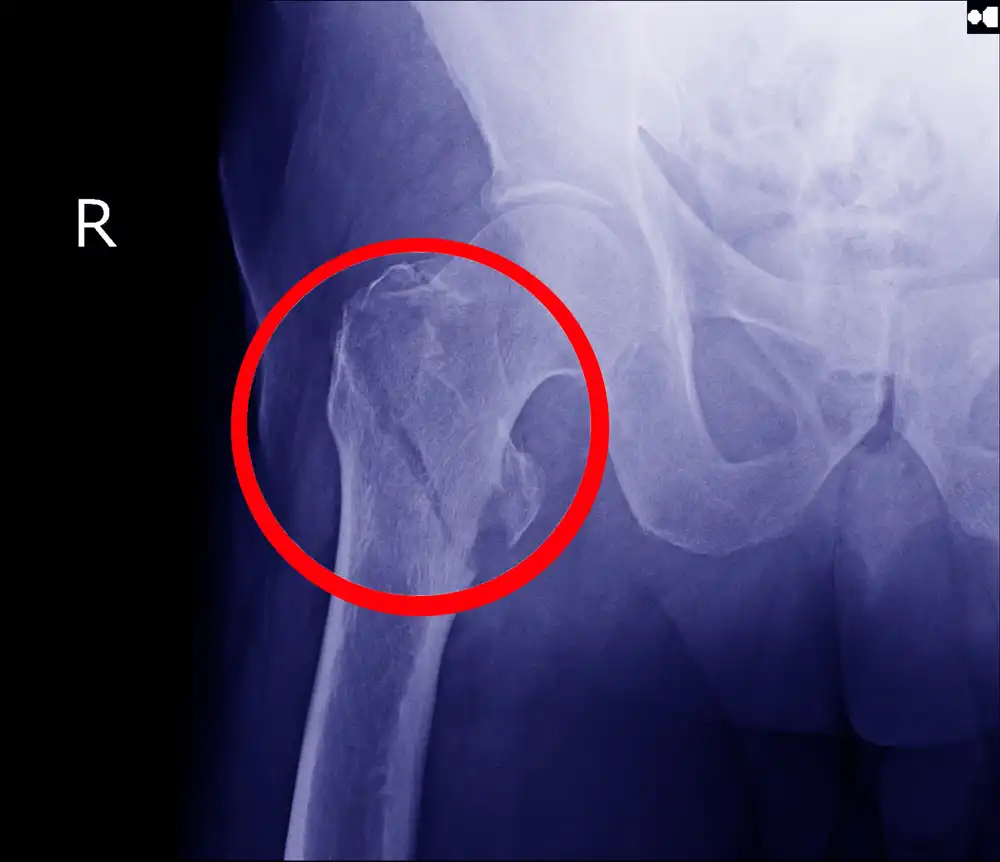

Fractures are bone cancer Symptoms, as bone cancer causes bones to weaken; which may lead to fractures sometimes, and then the person feels a sudden sharp pain in one of the limbs that have been suffering from pain for a few months due to cancer.

Previously swollen and painful bones can fracture; As cancer cells weaken bone density, and this fracture may occur spontaneously, or after an accident or a fall on it, and some radiation treatments may help reduce damage to the bones, and the attending physician may perform surgery to support the weak bone with a metal rod, and in the event of a bone fracture, it will be Surgically replaced with a solid steel piece.